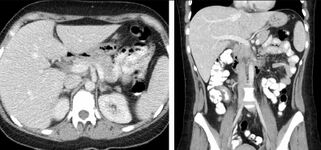

Non-contrast CT scans Figure 1a (left) and 1b (right) are of limited use for the differentiation of soft tissue structures. However, materials like blood, calcium (renal stones, vascular atherosclerosis), bone, and pulmonary parenchyma are highly visible and can usually be adequately assessed with non-contrast CT. For example, in the abdomen and pelvis, there are several indications for non-contrast imaging. These include: evaluation of renal calculi; assessment for gross intra-abdominal hemorrhage; and post-endostent volume measurements. In addition, non-contrast images are often obtained in conjunction with contrast enhanced images in evaluating potential renal transplant donors and in the evaluation of the pancreas (in combination with contrast phases). Of note, dual-energy CT and the development of virtual “non-contrast” images may ultimately obviate the combination scans. Additionally, CT angiography examinations performed for pathologies like aneurysms and dissection are frequently performed in conjunction with non-contrast imaging. The non-contrast images facilitate the differentiation of active extravasation or acute bleeding from vascular calcifications.[citation needed]

The most common technique is to perform portal venous phase imaging in the abdomen and pelvis (approximately 60–90 seconds after contrast administration, figure 2). This results in near optimal contrast opacification of the majority of the solid abdominal organs and it is used for a wide variety of indications: nonspecific abdominal pain; hernia; infection; masses (with a few exceptions such as hypervascular, renal, and some hepatic tumors); and in most follow-up examinations. As a general rule, this single phase is adequate unless there is a specific clinical indication that has been shown to benefit from other phases.[citation needed]

FIGURE 2. Contrast enhanced CT demonstrating parenchymal enhancement of the intra-abdominal organs in the portal venous phase (axial left, coronal reformat right).[citation needed]